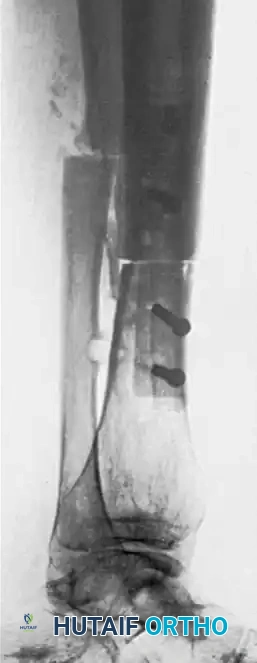

- Short Juxta-Articular Nonunions: When a nonunion occurs near a joint, the short metaphyseal fragment is often osteoporotic and difficult to control. The short fragment is grasped between the ends of the two grafts, with screws seated securely in the strong cortical bone of each graft, compressing the osteoporotic host bone between them.

The biomechanical superiority of the dual onlay graft lies in its vise-like compression and load-sharing capabilities.

When screws are inserted through the first cortical graft, through the osteoporotic host bone, and into the second cortical graft, the host bone is subjected to significant compressive forces. The dense cortical grafts act as massive washers, preventing the screw heads and threads from pulling through the weak host bone.

Furthermore, placing two cortical struts on opposite sides of the mechanical axis significantly increases the area moment of inertia, providing exceptional resistance to bending and torsional forces. The construct effectively bypasses the mechanically incompetent nonunion site, transferring loads through the rigid cortical grafts until creeping substitution and bony consolidation occur.